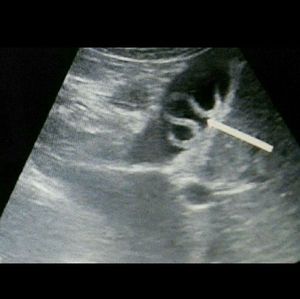

What is your diagnosis?

هذا براسيت اجل وهو بلهارسيا المسمى العام ليه ويسمى شستوسايمس . جاوبت عربي لان اتوقع انت عربية صح ؟🙂👍🏻

It’s a X-ray scan for Taenia in the bladder